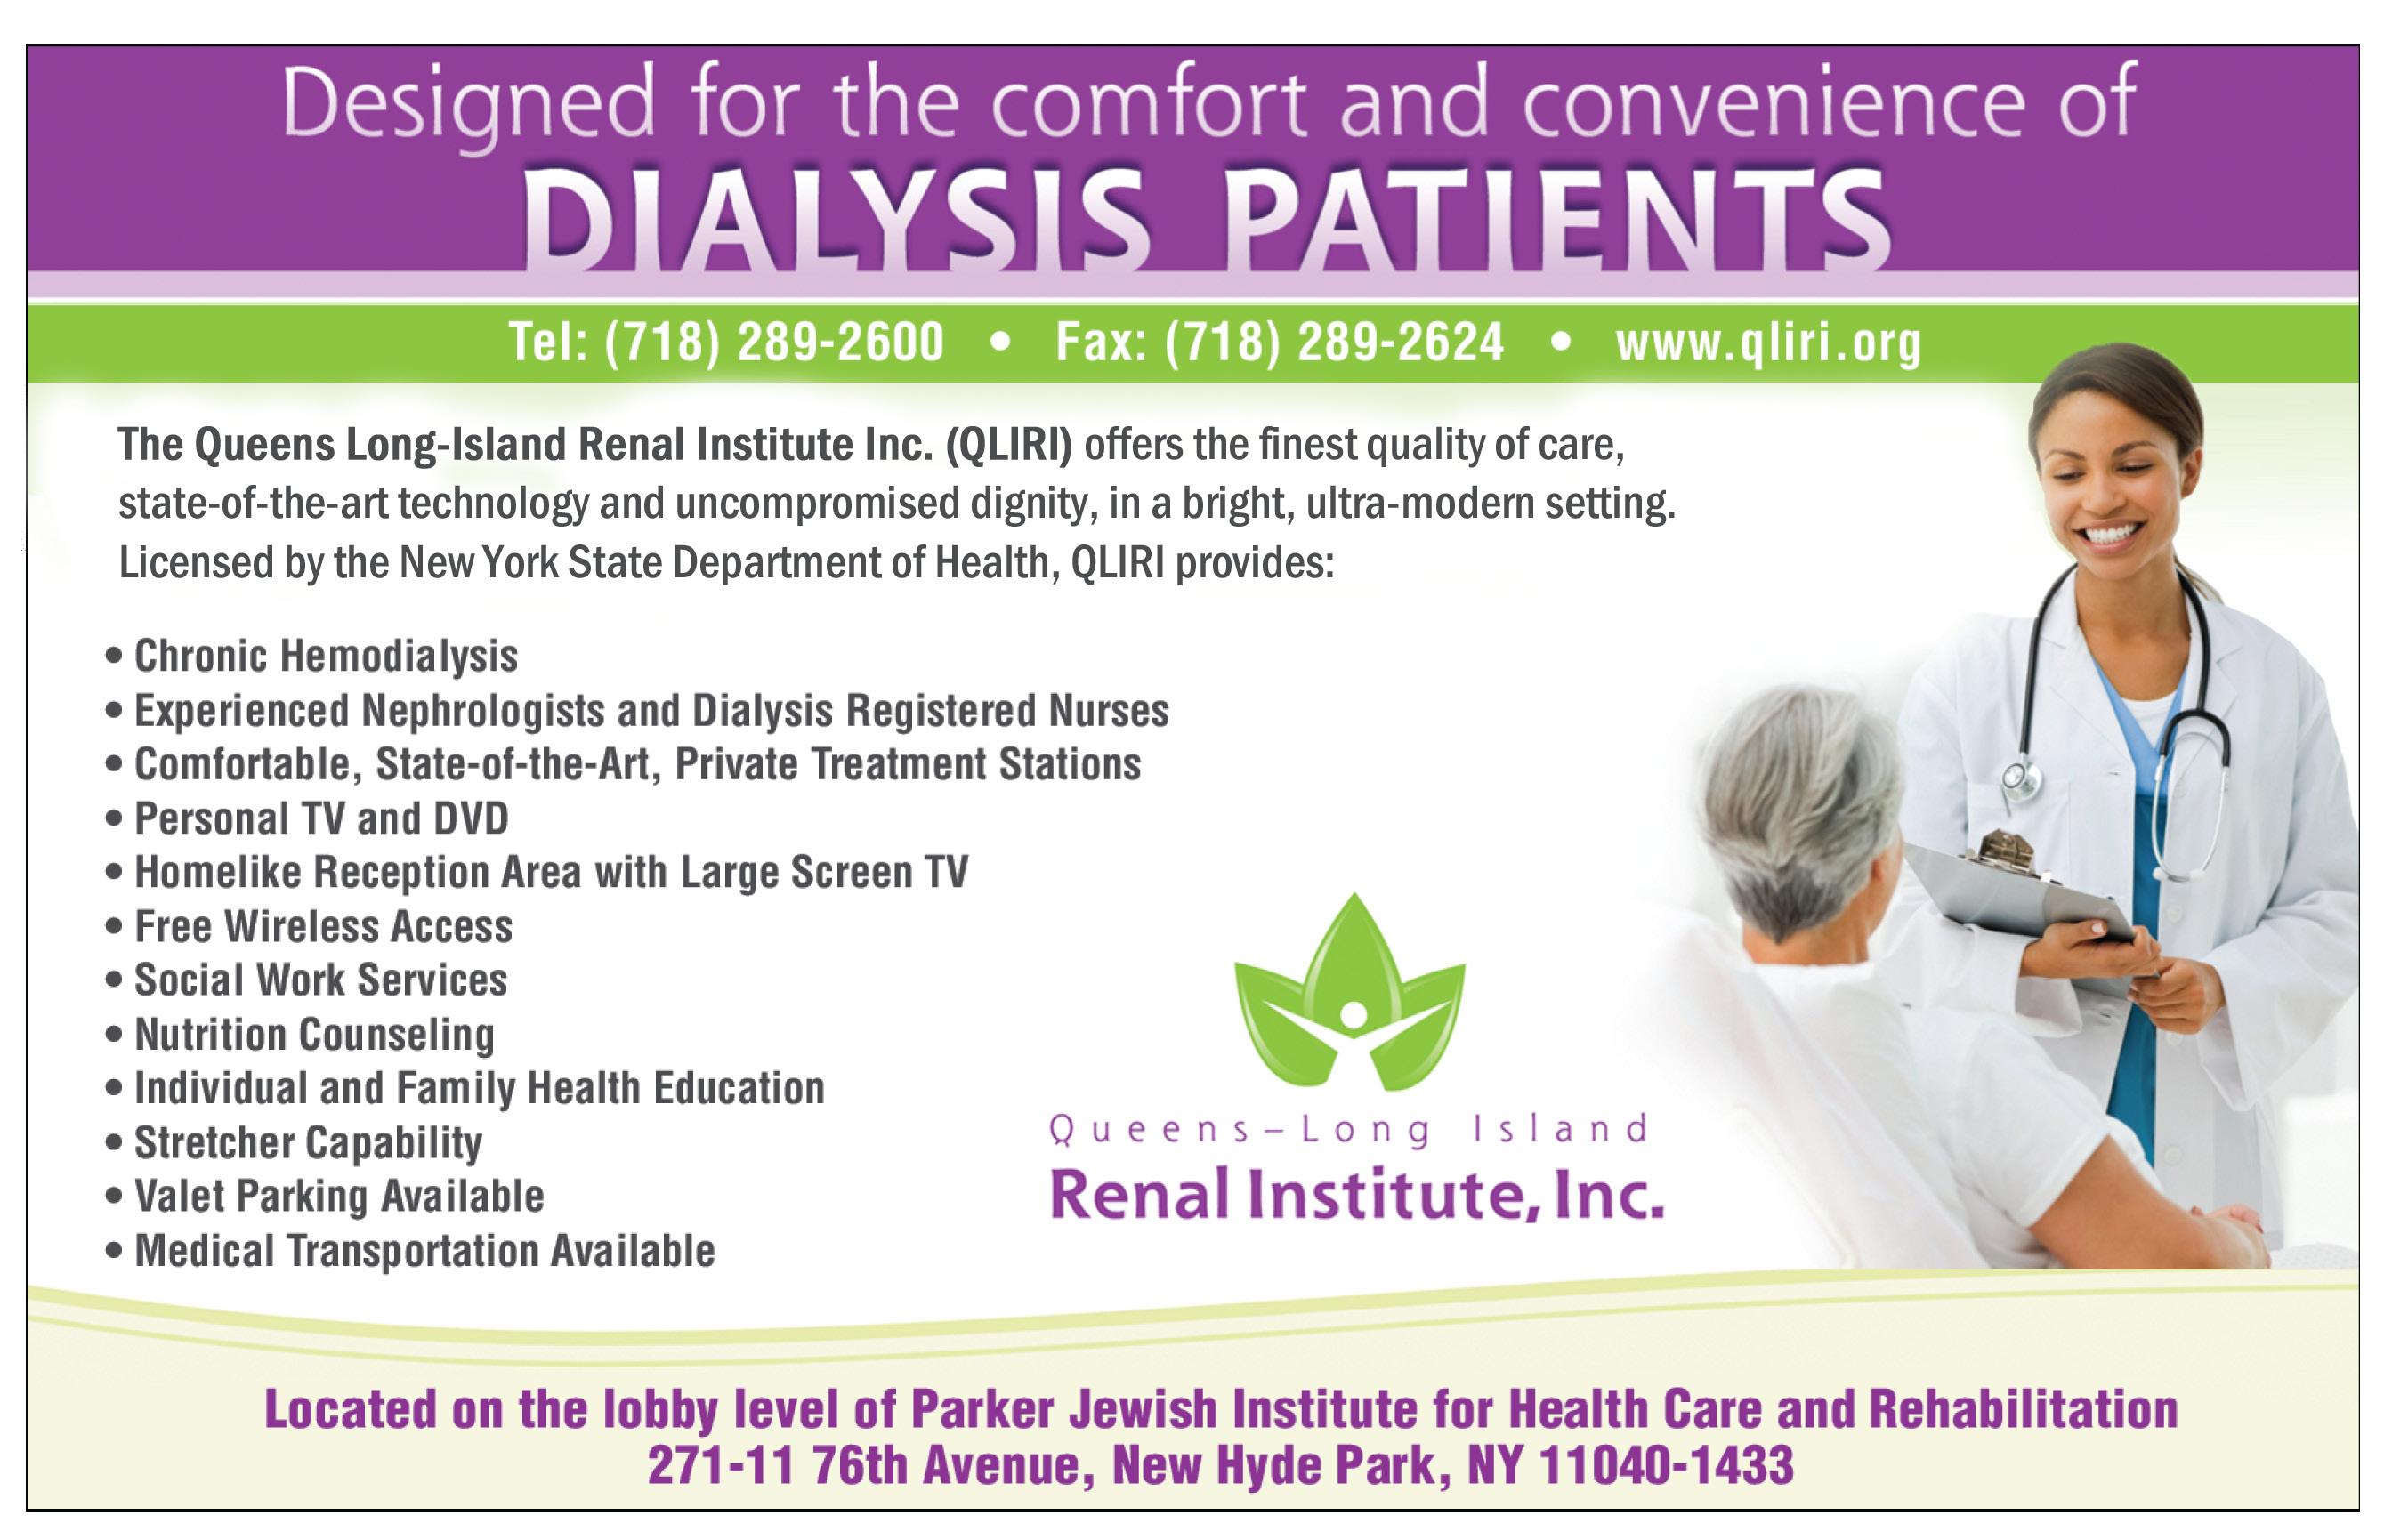

The Parker Jewish Institute is recognized with AJAS Jewish Programming Award

The Association of Jewish Aging Services awarded The Parker Jewish Institute with the 2022 Jewish Programming Award for its Family Call Center.

The award recognizes Jewish programs developed and implemented by AJAS organizations that are innovative, creative and specifically designed to enhance the spiritual well-being of the older adults they serve.

Early in the pandemic, Parker established its Family Call Center as a technology-based intervention, enabling patients and residents to connect with loved ones, and ensuring that family members quickly accessed essential information. In 2022, Parker adopted advanced technology to create new efficiencies, linking the Call Center to units within the Institute. This measure enhanced communications, so team members could expedite actions when needed and share information about Parker’s wideranging services.

Now, through the Call Center, families continue to easily get clinical updates on loved ones. Families reach out to the Call Center for information about social services and to communicate with social workers. Parker’s proactive Call Center team members connect with the

family of patients and residents on the day of admission, providing contact information and resources. They coordinate tours for potential patients, helping to simplify the admission agreements when needed.

“We are so proud to receive the AJAS 2022 Jewish Programming Award,” said Parker’s President and CEO Michael N. Rosenblut. “We continue to hone innovation at the Family Call Center, engaging team members and improving the quality of life for Parker’s residents, patients and their loved ones.”

About The Parker Jewish Institute for Health Care and Rehabilitation

The Parker Jewish Institute for Health Care and Rehabilitation is headquartered in New Hyde Park, New York. The facility is a leading provider of Short Term Rehabilitation and Long Term Care. At the forefront of innovation in patient-centered health care and technology, the Institute is a leader in teaching and geriatric research. Parker Jewish Institute features its own medical department, and is nationally renowned as a skilled nursing facility, as well as a provider of community-based health care, encompassing Home Health Care, Medical House Calls, Palliative Care and Hospice.

HEALTH MEMOS Parker Jewish Institute for Health Care and Rehabilitation • (718) 289-2212 • lscacco@parkerjewish.org Health memos are supplied by advertisers and are not written by Herald editorial staff. 1215195

From left: Susan Ryan of the Green House Project, the sponsor for programming awards; Rachel Dalton, Robert Sabella and Michael N. Rosenblut of Parker Jewish Institute; Don Shulman of Association of Jewish Aging Services; Lina Scacco of Parker.